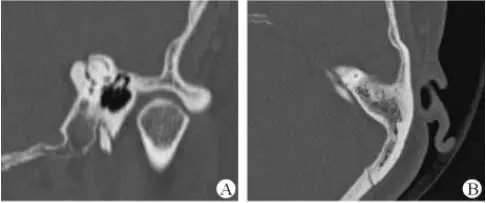

1、上半規(guī)管裂綜合征

內(nèi)耳結(jié)構(gòu)非常微妙。即使是內(nèi)耳中大頭針樣的孔洞也能造成平衡失調(diào)。患者常常不敢進(jìn)行如走路或轉(zhuǎn)頭的日常活動(dòng)。此罕見疾病,醫(yī)學(xué)專家預(yù)估至少影響著人口的1%。可造成惡心,眩暈以及對(duì)噪聲極高的敏感性。病人還常常抱怨他們能聽到血管跳動(dòng)的聲音。其中一位患者曾告訴耳科專家,他都能聽到自己轉(zhuǎn)動(dòng)眼睛的聲音。

診斷及治療

醫(yī)生若懷疑此病將會(huì)安排內(nèi)耳CT掃描。在大多數(shù)案例中,一旦此病被耳鼻喉科醫(yī)生或其它聽力健康專家確診,則可實(shí)行手術(shù)治療。外科手術(shù)風(fēng)險(xiǎn)包含聽力損失以及神經(jīng)損傷;重建及復(fù)原需內(nèi)耳的治療以及大腦的重塑。